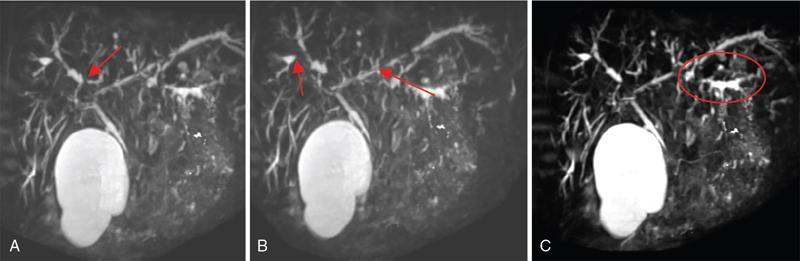

Ritu K. Kashikar, Shrinivas B. Desai, Chandresh Karnavat, Nilesh Doctor The biliary tract is subject to a variety of abnormalities. The spectrum includes benign diseases of autoimmune, infective, ischaemic, infiltrative aetiologies and malignant disorder, which most importantly represents cholangiocarcinoma. Imaging in particular magnetic resonance cholangiopancreatography (MRCP) plays a vital role in diagnosis and follow-up of these disorders. Multidetector computed tomography (MDCT) and magnetic resonance imaging (MRI) are also crucial in preoperative staging of biliary malignancies and making decisions regarding resectability and extent of resection. This chapter focuses on important benign and malignant disorders of the biliary tree and imaging features that aid in differentiation of various entities. A variety of disorders affect the biliary tree. Most biliary disorders manifest as biliary dilatation. The various causes are listed in Table 9.15.1. Imaging plays an important role in identification of aetiology based on pattern of involvement in association with clinical picture. USG is often the first investigation in a patient with jaundice. USG is excellent at showing biliary dilatation. It may be useless in assessing level of obstruction and biliary stones. Changes in liver morphology, development of cirrhosis is accurately done on USG. Early changes in conditions like primary sclerosing cholangitis (PSC), presence of intrahepatic ductal strictures, thickening of common bile duct (CBD) are, however, not confidently seen and need imaging modalities like MRCP and computed tomography (CT). Staging of hilar cancers is also best done on CT or MRI with contrast. Contrast-enhanced CT is extremely accurate in staging hilar cancers. It is a preferred modality to access radial spread of the disease and vascular involvement. Subtle changes of PSC and autoimmune cholangitis may however be missed and MRCP is preferred in these conditions. The protocol for evaluating biliary disease is standard plain scan followed by early, late arterial, portal venous and parenchymal phases similar to that obtained for focal liver lesions. Delayed phase images should be obtained for hilar malignancies, which often show delayed enhancement. MRCP with or without contrast is the modality of choice in diagnosing and characterizing biliary diseases. Owing to its noninvasive nature, it has replaced endoscopic retrograde cholangiopancreatography (ERCP) in the initial evaluation and follow-up of a variety of biliary pathologies. Absence of radiation exposure makes it suitable to obtain follow-ups in patients requiring serial scanning. The ability to diagnose abnormalities of both intra- and extrahepatic biliary tree, level of obstruction, longitudinal and radial spread of neoplastic process make it an ideal modality. MRCP protocol includes T2 weighted single-shot fast spin-echo, T1 weighted in phase and opposed phase gradient echo, diffusion-weighted imaging, T2-weighted fat-suppressed fast spin-echo in axial and coronal. A pre contrast three-dimensional T1-weighted fat-suppressed spoiled gradient-echo image is obtained in addition to 3-D MRCP. Postcontrast protocol includes dynamic three-dimensional T1-weighted fat-suppressed spoiled gradient-echo (in arterial, late arterial and portal venous, parenchymal and delayed phases). Since the advent and widespread use of MRCP, the utility of ERCP in diagnosing biliary pathologies has significantly reduced. ERCP is primarily used when stenting or other procedures need to be performed in the same setting. Although an invasive procedure with postprocedural risk of pancreatitis ERCP allows excellent depiction of biliary changes in conditions like PSC, recurrent pyogenic cholangitis (RPC) and IgG4-related disorders. Endoscopic USG (EUS) is an excellent modality in diagnosing lower bile duct pathologies and also has the added advantage of obtaining a biopsy in the same setting. EUS is less invasive than ERCP and overall safer. PSC is a premalignant cholestatic liver disorder characterized by bile duct strictures secondary to bile duct inflammation and fibrosis. Cirrhosis of liver can develop secondary to this condition and patients are at a high risk for biliary and colonic cancers. PSC is a relatively rare disease, with an incidence of less than 50 per 100,000 patients though it varies in various location. It is diagnosed in young patients aged 30–40 years and is twice as common in men than in women. Similar to other autoimmune diseases, genetic susceptibility is likely to be instrumental in the development of PSC after exposure to a trigger. There is also a strong association between PSC and human leukocyte antigens (HLAs). Environmental factors such as childhood microbial exposure also play an important role in disease pathogenesis. A strong association of PSC with inflammatory bowel disease (IBD) is seen. There is a 100-fold increased risk of developing PSC among siblings. PSC can be asymptomatic but may present with cholestatic symptoms such as jaundice, pruritus, fatigue and right upper quadrant pain, steatorrhoea and episodes of acute bacterial cholangitis. There is marked elevation of alkaline phosphatase (ALP). A twofold to threefold increase in serum alanine and aspartate aminotransferase (AST) can be seen. Elevated bilirubin is usually seen in advanced disease, malignancy or those with choledocholithiasis. Various serum antibodies can also be elevated in PSC. These have been enlisted in Table 9.15.2. On liver biopsy, classic pathologic features of periductal concentric fibrosis or ‘onion skin’, around the affected ducts can be seen. This is however not a pathognomonic finding and is seen in less than 40% of biopsy specimens. Therefore, biopsy is not routinely used as a diagnostic tool for PSC and is reserved primarily for disease staging. MRI with MRCP best depicts the biliary changes in PSC and is the modality of choice. While CT and USG may show biliary dilatation and changes of cirrhosis in advanced cases, they fail to show early changes (Table 9.15.3). USG is an effective modality for the visualization of dilatation and diffuse wall thickening of the extrahepatic bile duct. Other feature seen on USG is bright echogenic portal triad. However, the role of USG in the diagnosis of early PSC is limited owing to suboptimal assessment of the intrahepatic biliary ducts. Features of advanced disease such as heterogeneous coarse echogenicity can be readily detected with USG. The major benefit of performing US is to guide liver biopsy. Also, liver stiffness as assessed by transient elastography correlated well with the degree of liver fibrosis in PSC patients. CT can demonstrate some findings suggestive of sclerosing cholangitis such as focal, discontinuous, often peripheral intrahepatic biliary duct dilatation and thickening with enhancement of the bile ducts owing to inflammation. CT is effective in helping exclude other causes that can result in biliary stasis and dilatation such as hepatic and pancreatic lesions. CT is also excellent in diagnosing tumours, which may sometimes have similar presentation. Concomitant changes of IBD, if present, can be seen. However, CT is limited in assessment of biliary strictures and visualization of disease involving small peripheral bile duct, especially in the early stages of the disease. CT shows changes of cirrhosis in liver and assessing changes of portal hypertension. MRCP is diagnostic imaging modality of choice in the workup of patients with suspected PSC, as recommended by both the AASLD and EASL guidelines. MRCP has high diagnostic sensitivity (86%) and specificity (94%) for the detection of PSC (Table 9.15.3). Multifocal short segmental strictures in the intra- or extrahepatic biliary tree with intervening normal or dilated duct leading to beaded appearance are seen in early disease. The location in strictures is usually at the biliary bifurcation and are disproportionate to upstream dilatation. Advanced cases show pruning of peripheral biliary radicals secondary to advancing fibrosis obliterating the smaller ducts. An obtuse angle between the central and peripheral ducts is suggestive of PSC. Diverticula and webs also can be seen, though not pathognomonic (Table 9.15.4) (Figs. 9.15.1–9.15.3). Strictures of the CBD of less than 1.5 mm and of left, right or common hepatic duct (CHD) of less than 1 mm are defined as dominant stricture. A dominant stricture is associated with worse prognosis in part due to development of cholangiocarcinoma. MRCP plays an important role in raising the suspicion and guiding treatment. A dominant stricture may be confused with hilar cholangiocarcinoma on imaging and it is often impossible to distinguish the two based on imaging alone (Table 9.15.4) (Fig. 9.15.4). Changes in liver morphology are seen in the form of distortion. The classical change described in PSC includes hypertrophy of the caudate lobe and atrophy of the left lateral and right posterior segments of the liver. Hypertrophy of caudate lobe is more frequent in PSC than cirrhosis from other aetiologies. Other parenchymal changes include heterogeneity of liver, periportal cuffing, peripheral inflammation, cirrhosis and features of portal hypertension. Hyperintensity of the liver parenchyma in PSC on nonenhanced T1-weighted images has been reported. Wedge-shaped peripheral atrophic areas of confluent hepatic fibrosis are seen as high T2-weighted signal intensity. Periportal oedema is visualized as high signal intensity in periportal region on T2-weighted. Increased heterogeneous peripheral enhancement of the liver parenchyma can be seen and is likely due to the altered blood supply in those areas in response to parenchymal inflammation (Table 9.15.4) (Figs. 9.15.5 and 9.15.6). MR elastography is the most accurate noninvasive method for the diagnosis and staging of liver fibrosis and could potentially replace liver biopsy. It is predictive of progression to decompensated liver disease. However, lack of wide availability are still major limiting factors. MR elastography is not influenced by obesity or anatomical conditions (e.g. narrow intercostal spaces and ascites) and the sample size of the liver is significantly higher and hence has several advantages over ultrasound elastography (Table 9.15.5). Besides these features, enlarged reactive abdominal lymph nodes, commonly periportal and portocaval lymph nodes, are commonly diagnosed in PSC and should not be misdiagnosed as a lymphoproliferative disorder or metastatic disease. Though ERCP has higher diagnostic accuracy in detecting PSC, its role is limited to intervention required in PSC due to its invasive nature and potential complications. Also it is recommended that MRCP be performed prior to ERCP as a preprocedural MRCP can provide a road map to the endoscopist. Small duct PSC is a variant PSC syndrome with biochemical markers and histologic features suggestive of PSC with normal cholangiography. It is associated with better prognosis. Approximately one-fourth of patients’ progress to classic PSC in an average of 8 years. Bile duct calculi are a common complication of PSC. Pigmented bile duct stones are common owing to biliary stasis. Both intrahepatic and extrahepatic biliary stones can be found. However, the presence of biliary tree stones is not an essential diagnostic feature. Soft calcific foci within dilated bile ducts can be seen on US and CT images. MRI with MRCP is the imaging modality of choice to detect bile duct stones and appear as focal areas of signal-intensity-void filling defects on T2-weighted images. Usually isointense at T1-weighted imaging but frequently are hyperintense. The presence of biliary strictures puts these patients at risk of bacterial cholangitis in PSC patients. The classic Charcot triad of fever, abdominal pain and jaundice can be seen. Early enhancement of the biliary wall due to the biliary duct inflammation is a common finding with peribiliary reactive hepatic parenchymal changes. Cholangitic abscesses may sometimes be seen. PSC patients are at high risk of developing cholangiocarcinoma during the disease course with and a total risk of 10%–15%. Approximately 30% of all cholangiocarcinomas are detected within the first year of establishing a diagnosis of PSC and so it is important to be suspicious even at the time of PSC diagnosis and to survey for early detection. Rapid clinical deterioration, worsening of jaundice, pruritus, weight loss along with elevation in serum bilirubin and ALP should raise suspicion of PSC. It may be difficult to distinguish benign from malignant strictures. Progressive bile duct wall thickening, irregularity, enhancement, new onset biliary dilatation, dominant stricture or development of focal strictures with dilatation and ipsilateral atrophy are indeterminate features that may raise possibility if occult cholangiocarcinomas. Perivascular thickening, vascular involvement or occlusion are features favouring malignancy. Definite diagnosis is however often not possible on imaging alone and a brush biopsy should be taken in patients with new onset clinical symptoms, elevated tumour makers or above-mentioned indeterminate imaging features (Table 9.15.7). The most common subtype of cholangiocarcinoma in PSC patients is periductal type, characterized by long segment irregular wall thickening along the bile duct with no identifiable mass. The lesion is hypointense on T1W1 images and hyperintense on T2W1 images showing progressive enhancement on contrast study. The tumour could be at the bifurcation and can cause abrupt cut-off, commonly presenting as Klatskin tumour (Fig. 9.15.7). Combined UC and PSC is associated with a higher risk for colorectal carcinoma than UC alone. PSC is considered as an independent risk factor for development of colorectal carcinoma in patients with UC. Malignancy tends to involve the right colon or more proximal parts of the colon. Clinical presentation and history in patients with ascending cholangitis differ from those with PSC. Fever, pain and jaundice dominate the presentation in patients with ascending cholangitis while patients with PSC may be asymptomatic. The typical findings of PSC including biliary duct stenosis, beading or pruning are not typical findings in the newly diagnosed cases of acute ascending cholangitis. Wedge-shaped peripheral and/or intrahepatic peribiliary foci of increased T2 signal around the dilated radicals with arterial and/or delayed parenchymal enhancement has been described in ascending cholangitis. Patients with RPC present with recurrent episodes of abdominal pain, fever, jaundice and chills. These features differ from those in patients with PSC. Hepatolithiasis with pigmented stones in the biliary tree and upstream and downstream duct dilatation are typical imaging features in RPC (Table 9.15.8). Ischaemic cholangiopathy is a form of biliary injury resulting from decreased arterial supply. History of liver transplantation is the key in diagnosing ischaemic cholangiopathy. Biliary strictures in AIDS cholangiopathy are indistinguishable from PSC. However, the combination of papillary stenosis and intrahepatic ductal strictures appears relatively unique to AIDS cholangiopathy; this combination is not found in PSC. Clinical history may help to distinguish one from the other. Effective medical therapy for PSC is lacking. Oral ursodiol (ursodeoxycholic acid) is one of the main treatment options of cholestatic diseases though does not prevent disease progression. Azathioprine and steroids are recommended for use in patients with AIH as well as those with AIH–PSC overlap syndrome. Vedolizumab is a gut-specific monoclonal antibody that has been tried but the clinical utility in PSC–IBD patients remains under investigation. Dilatation of biliary strictures, stenting, lithotripsy and stone extraction can be done with the aid of ERCP and percutaneous transhepatic cholangiography (PTC). The only definitive cure of PSC is, however, liver transplantation. Treatment of complications like choledocholithiasis stone removal can be accomplished by using standard endoscopic techniques with or without sphincterotomy, with balloon or basket extraction for extrahepatic biliary stones. For bacterial cholangitis, immediate administration of broad-spectrum antibiotic therapy is recommended and in abscess formation percutaneous drainage with intravenous antibiotic therapy shows favourable outcome compared with surgical drainage. Incidence is 20%–25%. Diagnosis of recurrent PSC requires careful evaluation, as there are other causes of biliary changes after liver transplant with similar features. Nonanastomotic biliary strictures imply the diagnosis of recurrent PSC only if they occur more than 90 days after transplant. Characteristic multifocal strictures and segmental dilatations of biliary ducts are suggestive findings. MRCP is the initial modality. RPC is characterized by a triad of recurrent biliary sepsis, inflammatory biliary strictures and intrahepatic stones. Fifty per cent of patients may have acute pancreatitis. Oriental cholangiohepatitis, primary hepatolithiasis, Hong Kong disease and oriental infestational cholangitis. Prevalence in the third and fourth decades of life with equal frequency among men and women peak. Southeast Asia predominantly in rural population and in lower socioeconomic groups. Gut-derived organisms lead to sepsis, which initiates a cascade of events, which leads to a chronic, progressive and recurrent inflammatory process in cholangioles. Associations with Clonorchis sinensis, Opisthorchis species, Fasciola hepatica and Ascaris lumbricoides infestations have been suggested. Common organisms cultured from bile include Escherichia coli, Klebsiella, Pseudomonas and Proteus species and anaerobes. Structural biliary abnormalities may develop before stones are demonstrable. Strictures may be seen at cholangiography without stones and vice versa. Entrapped stones cause stasis, sepsis, scarring and stricturing with the increasing lithogenicity (Table 9.15.9). Typically present with abdominal pain, fever and jaundice (the Charcot triad) and commonly provide history of repeated episodes. Routine investigations may demonstrate leukocytosis, deranged liver enzymes with obstructive pattern. Elevated cholestatic markers (bilirubin, ALP and gamma GT) and deranged LFTs can be seen. Serum inflammatory markers can be elevated. Additional tests aiding in differential diagnosis include autoantibodies, ANCA, CA19-9 and serologic tests for Echinococcus. Histology is usually not required. It shows fibrous mural thickening of bile ducts and periductal tissue, as well as acute and chronic inflammatory changes. The imaging features include changes in bile ducts, development of calculi and changes in the parenchyma. The disease affects intrahepatic ducts more than the CHD and CBD. Disproportional dilatation of central intrahepatic ducts and extrahepatic bile ducts is seen with nondilated or minimally dilated peripheral ducts, leading to abrupt tapering of bile ducts. All segments of biliary tree may be involved, but the lateral segment of the left lobe is most often and extensively involved most likely because left hepatic ducts come off at a more acute angle compared with the right hepatic ducts, thus predisposing to stasis and stricture formation (Table 9.15.10). Hepatolithiasis is common in patients with RPC. Stones are composed mainly of bile pigments with variable calcification. There may be single or multiple stones scattered in the intra- or extrahepatic ducts or both. The dilatation of the extrahepatic duct is generally not related to the location of the stone. Ducts both proximal and distal to the stone are dilated. Parenchymal atrophy most commonly involves the left lateral and right posterior segments while hypertrophy of the caudate and right lobe is seen. USG shows dilatation of the central intrahepatic and extrahepatic ducts, with relative sparing of the peripheral biliary tree. Hepatolithiasis can be seen in 90% of cases. The echogenicity and acoustic shadowing of calculi may vary depending on extent of calcification. There is often associated periportal echogenicity. Ultrasound may be useful in performing image-guided percutaneous drainage of abscesses or biopsy of suspicious lesions. Limitations include inability to detect subtle intrahepatic ductal dilatation and heavy stone burden obscuring evaluation of underlying hepatic parenchyma. Contrast-enhanced CT is increasingly being used as first line of imaging. It allows for detection of characteristic disproportionate dilatation of the extrahepatic and central intrahepatic ducts. Contrast-enhanced CT also allows for detection of bile duct wall enhancement, suggestive of acute cholangitis. Ninety per cent stones are hyperdense to liver parenchyma on nonenhanced scan. Extent of calcification in calculi may vary. Parenchymal atrophy affects left lateral segment most frequently, followed by right posterior segments. Eventually, changes of cirrhosis can be seen. Heterogeneous appearance of liver parenchyma with segmental steatosis and altered enhancement can be seen particularly during acute attack. Pneumobilia is not infrequent and can usually be attributed to recent procedures or surgeries like bilioenteric anastomosis. It may, however, be seen in patients without history of prior interventions due to recent passage of stone through the ampulla or less commonly cholangitis related to gas forming organisms (Fig. 9.15.8). Subtle intrahepatic ductal strictures and noncalcified stones may be missed on CT. MRCP allows visualization of both intra- and extraductal disease and can reveal complete extent, severity and complications of the disease. Even noncalcified calculi which may be missed on CT or sonography, are seen as intraductal filling defects on heavily T2-weighted images and may appear hyperintense to the liver on T1-weighted images. MRI demonstrates central and extrahepatic duct dilatation with decreased arborization and abrupt tapering of peripheral ducts. MRI particularly MRCP sequences accurately depicts stenotic segments and delineates the entire biliary tree, including the proximal part of the stricture, without risk of aggravating biliary sepsis. Even short segment duct strictures <1 cm are easily seen on MRCP (Figs. 9.15.8 and 9.15.9). Parenchymal abnormalities like hepatic atrophy, whether diffuse or segmental, and altered signal can be accurately diagnosed. Mass lesions and hepatic abscesses, if present, are also well delineated. The characteristic finding of disproportionate dilatation of the ducts, with multiple intraductal calculi are well demonstrated. There may also be intrahepatic strictures, with abrupt tapering of the peripheral ducts as well as decreased arborization of the biliary tree (arrowhead appearance). It allows for better spatial resolution, thus permitting better evaluation of the smaller peripheral ducts. The main limitation of ERCP is its invasive nature, with complications such as ERCP-associated pancreatitis. Heterogeneous parenchymal enhancement, wall thickening and periductal enhancement are seen in acute cholangitis. Abscess formation is encountered in up to 20% of RPC patients who undergo cross-sectional imaging. The abscesses can occur in both the affected and unaffected portions of the liver but most commonly seen in the right lobe. Sonography guided aspiration can be done when diagnosis is doubtful. Intrahepatic bile lakes are not infrequent and may or may not communicate with the biliary tree. On USG bilomas appear anechoic and are usually hypodense on CT with or without calculi. Leakage of bile from a severely dilated obstructed duct may lead to formation of extrahepatic biloma. Cholangiocarcinoma is the most feared complication and may be seen in up to 5% of patients. Segments with high stone burden or those with atrophy are more prone to developing cholangiocarcinoma. Clinical and laboratory indicators for development of cholangiocarcinoma in patients with PSC include increase in jaundice without associated cholangitis, sudden weight loss, significant elevation of ALP and rising tumour markers. Peripheral cholangiocarcinoma manifests as expansion of the affected segment. Hypoattenuating mass with showing peripheral enhancement causing narrowing of the portal vein may raise suspicion of malignancy. Portal vein thrombosis has also been reported but is rare. Recurrent biliary sepsis may lead to periductal inflammation and portal thrombophlebitis. Portal thrombosis can lead to lobar atrophy with compensatory hypertrophy of the uninvolved lobe. Higher incidence of hepatocellular carcinoma (HCC) is reported in patients with RPC due to development of cirrhosis in severe cases. Management should comprise antibiotic treatment, clearance of stones, maintenance of biliary drainage and long-term follow-ups. ERCP allows for therapeutic procedures such as stone removal and stenting of strictures. Destroyed liver segments, those with multiple abscesses and patients with secondary cholangiocarcinoma are candidates or surgery. Stone extraction can also be done surgically with the aid of basket, forceps, balloon catheter or flexible choledochoscope. Transduodenal sphincteroplasty and hepaticojejunostomy are commonly performed drainage procedures. Indications for transplantation include extensive bilobar hepatolithiasis, cirrhosis and liver failure. IgG4 cholangiopathy is a cholangitis characterized by elevated serum IgG4 and infiltration of the bile duct wall with IgG4 positive plasma cells leading to storiform fibrosis and obliterative phlebitis with resultant bile duct wall thickening. This condition shows good response to steroids. Frequent association with IgG4-related autoimmune pancreatitis is seen. IgG4 sclerosing cholangitis (IgG4-SC) has a threefold to fivefold higher prevalence in men than women. It usually presents in the fifth and sixth decades of life. Incidence of this disease is approximated to be around 0.28–1.08/100,000. Autoimmunity has been considered as the most probable pathogenesis of IgG4-related disease (IgG4-RD). Several HLA association have identified as determinants of disease susceptibility. The major histologic features associated with IgG4-RD have been well described and include the steps. Chronic or recurrent cholangitis is the most common presentation and seen in up to 75% cases. Other symptoms seen are fever, pruritus, pain and weight loss. Biliary involvement may be detected incidentally in patients being scanned for symptoms related to involvement of other organs such as pancreas. One-quarter of patients with IgG4-SC may be asymptomatic. Serum liver tests show a cholestatic pattern with often marked elevation of ALP and γ-GT and only mildly increased ALT and AST. Serum bilirubin may be increased. Tumour marker CA 19-9 is not able to distinguish pancreatobiliary malignancies from IgG4-SC since levels of >1000 IU/mL (ULN = 37 IU/mL) may be observed in IgG4-SC. IgG4 levels are elevated (>140 mg/dL) in up to 75%–80% of affected patients. A cut-off level of 207 mg/dL might be useful for completely distinguishing IgG4-SC from cholangiocarcinoma. Elevated bile fluid IgG4 has a high sensitivity and specificity of 100% at a cut-off level of 113 mg/dL and seen only in cases of IgG4-RD, neither PSC nor cholangiocarcinoma. Approximately 40% of patients have peripheral blood eosinophilia, often accompanied by asthma and atopy. Patients may show hypergammaglobulinemia, elevated serum IgE. Several diagnostic criteria have been developed to aid in the diagnosis of IgG4-SC. The most widely used is the HISORt (Histology, Imaging, Serology, other Organ involvement and Response to therapy) criteria of the Mayo Clinic. This tool was initially used to diagnose AIP but can be adapted to diagnose IgG4-SC by Ghazele et al. (Tables 9.15.13 and 9.15.14). It is often the initial investigation and may be normal early in the course of the disease. Circumferential thickening of the bile ducts with biliary dilatation is seen later in the disease. US also helps in the identification of associated findings affecting other organs. However, US has low sensitivity in detecting the disease and is suboptimal for assessing the extent of the disease. Contrast-enhanced CT though not the investigation of choice shows bile duct wall thickening with proximal mild dilatation. The intrapancreatic bile duct segment is more commonly involved. The most important finding is circumferential symmetric wall thickening of the bile ducts, frequently involving the extrahepatic segments, with smooth outer and inner margins. In addition, the thickened segment shows progressive homogeneous contrast enhancement, further increasing in the delayed phase. As opposed to malignancies, wall thickening or stricturing of bile ducts in IgG4-RD is not associated with proportionate proximal biliary dilatation (Figs. 9.15.10 and 9.15.11). In addition to the above findings, imaging findings of IgG4 disease affecting other organs, that is, gallbladder wall thickening, changes of autoimmune pancreatitis, retroperitoneal fibrosis and kidney findings can be seen. MRI is the investigation of choice. MRI findings are similar to CT findings and include circular and symmetric long segmental thickening of the bile duct wall with smooth outer and inner margins. Bile duct wall thickening can be seen in nonstenotic areas as well The other findings are the visibility of patent bile duct in the strictures, disproportionate proximal dilatation, hyperenhancement during the late arterial phase, homogeneous hyperenhancement during the delayed phase, concurrent gallbladder wall thickening and no vascular invasion (Table 9.15.15).